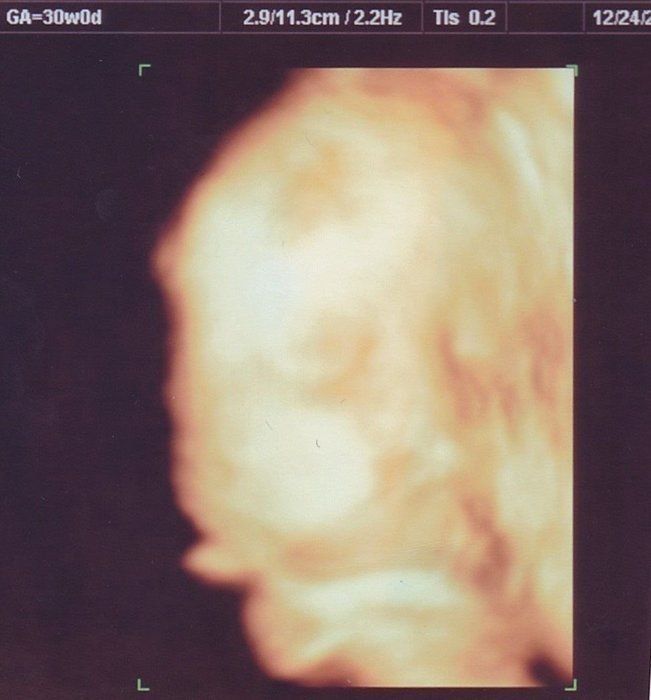

なつさんの妊娠30週目のエコー写真

どんな顔かわかるようになってきました

エコーで顔立ちがはっきり見られるようになりました。チェックしているときにしゃっくりをしていたのも見られました。恒例になっていたおしりチェックをしてもらうと、突然おしりの間に男の子のしるしが! 「今までの検診で何度も見ていたのに、どうして急にわかったんだろう」と家族と驚きました。